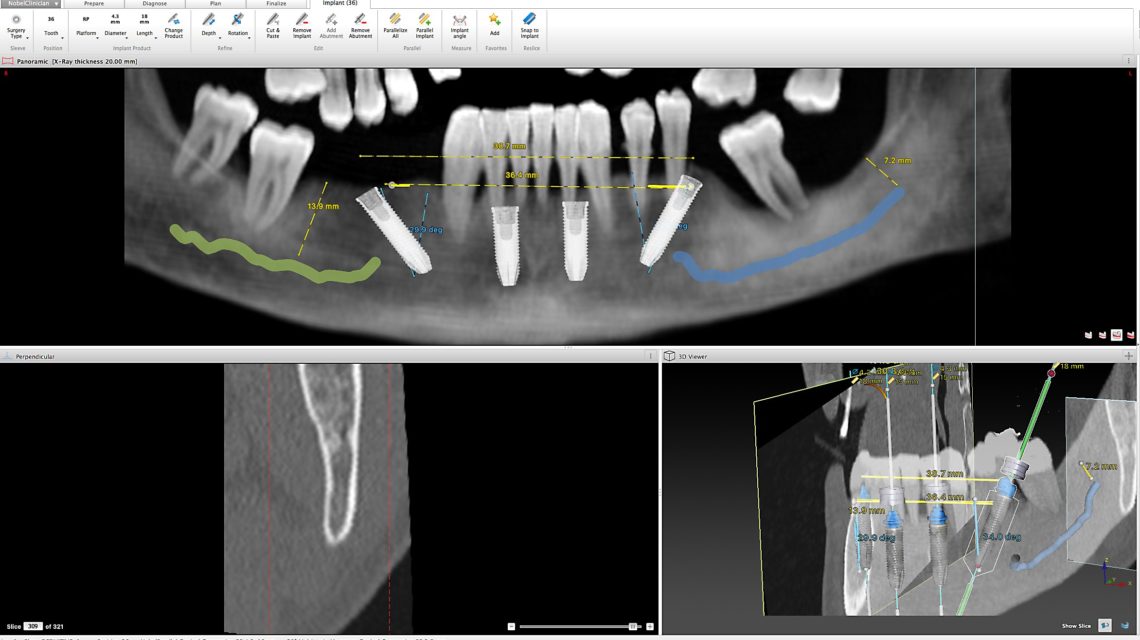

Caso Clínico: Reabilitação total bimaxilar com 10 implantes e 2 próteses híbridas

Descrição: Paciente com 65 anos residente em Macau que pretende uma reabilitação total com implantes no prazo máximo de 8 meses. O tratamento constituíu na extração de todas as peças dentárias, colocação de 6 implantes no maxilar superior e 4 no maxilar inferior culminando com a colocação de 2 próteses híbridas aparafusadas.